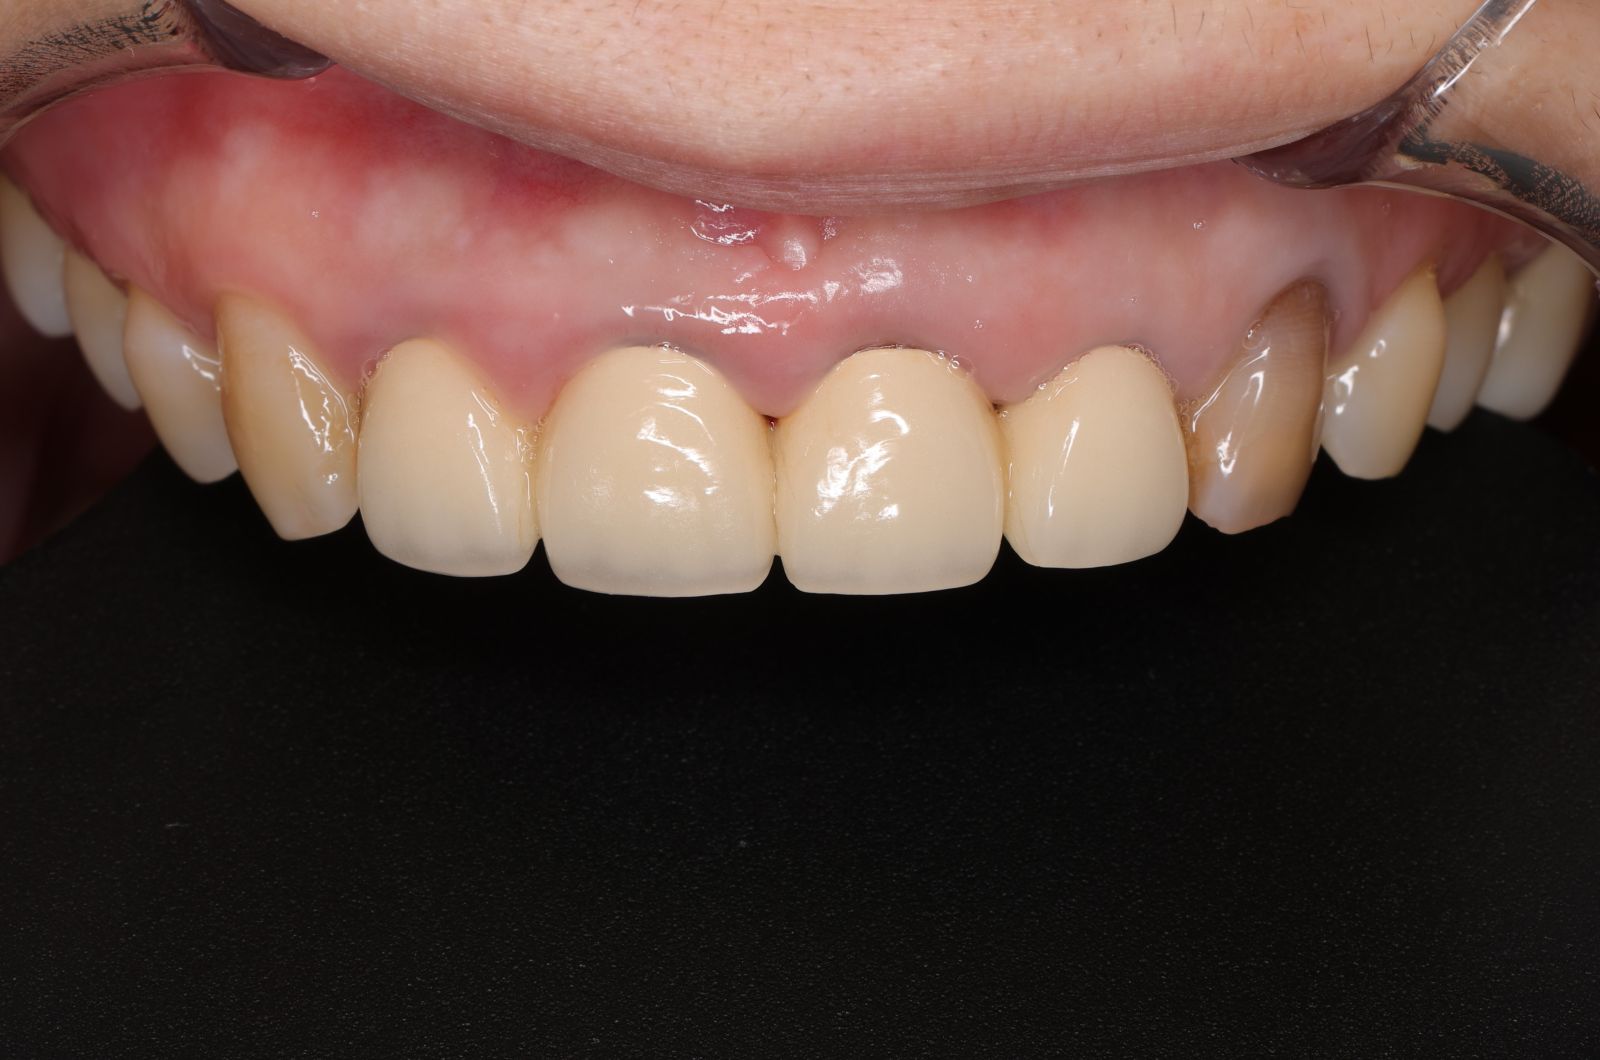

經過數位微笑曲線設計,選擇自己喜歡的色階後就可以製作適合自己的美學全瓷牙囉!全瓷冠經過特殊處理呈現的通透感,讓牙齒白而自然透亮。